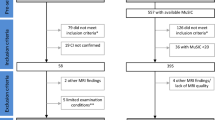

Patients

Twenty-six patients with a diagnosis of probable MSA, of which 14 with the parkinsonian variant (MSA-P) and 12 with the cerebellar variant (MSA-C), according to current criteria [1] were enrolled at the Center for Neurodegenerative Diseases of the University of Salerno between November 2015 and April 2019. All patients underwent a neuropsychological battery, motor test, and magnetic resonance imaging (MRI) at baseline (T0) and at follow-up (T1), 12 months later. The local Ethics Committee approved the study, and all patients signed informed consent.

Patients were divided according to cognitive status in MSA with normal cognition (MSA-NC) and MSA with mild cognitive impairment (MCI), including both patients with MCI-single domain (MSA-sd) and with MCI-multiple domain (MCI-md). Due to the lack of specific criteria for the diagnosis of MCI in MSA, it was diagnosed according to the MDS criteria for MCI in Parkinson’s disease [9]. At T1, we divided the sample according to worsening/nonworsening of cognitive status from T0 to T1.